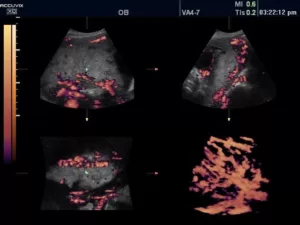

D-режим (допплерография)

Допплерография используется для неинвазивного изучения характеристик движения тканей и жидкостей в организме человека. Наибольшей информативностью этот формат сканирования обладает в диагностике сердечно-сосудистой и акушерско-гинекологической патологии.

Принцип работы режима основан на эффекте Доплера — физическом явлении, представляющем собой изменение частоты отраженного сигнала в зависимости от скорости движения изучаемого объекта. Частота увеличивается с приближением к датчику и снижается при удалении от него. В роли объектов, отражающих эховолны, обычно выступают эритроциты.

Благодаря D-режиму и его разновидностям можно исследовать основные параметры кровотока (направление, скорость, ламинарность), оценить степень васкуляризации патологического очага.

Сканирование, одновременно сочетающее одну из доплеровских методик и визуализацию в В-режиме, называется дуплексным. Оно позволяет получить комплексную информацию об анатомии сосуда (структуре его стенок, диаметре просвета), определить качественные и количественные характеристики гемодинамики. Кровоток, направленный к датчику, картируется оттенками красного цвета, от датчика — в синей цветовой палитре. Турбулентный кровоток отображается в сине-желто-зеленых тонах.

Триплексное сканирование — сочетание В-режима с двумя допплеровскими режимами (к примеру, спектральным и цветовым).

21.jpg

Рис.2. Почка в режимах CFI и PW.

Режим CFI (Color Doppler Imaging, ЦДК, цветовое допплеровское картирование)

Цветовой доплеровский режим позволяет анализировать характеристики кровотока не только в формате графика на осях, но и в виде цветной схемы. На ней красным цветом выделяются потоки крови, идущие по направлению к датчику, а синим — в противоположную от него сторону. Насыщенность оттенка свидетельствует о скорости движения эритроцитов: чем она ниже, тем ярче изображение.

23.jpg

Рис.3. Пуповина плода в режиме ЦДК + LumiFlow (программное обеспечение, устанавливаемое в ультразвуковом аппарате высокого разрешения).

Поскольку исследование в режиме CFI на большой области обладает ограниченной информативностью, спектральная доплерография предоставляет более детальные данные о небольшом участке, оба режима дополняют друг друга и в практической работе применяются совместно.